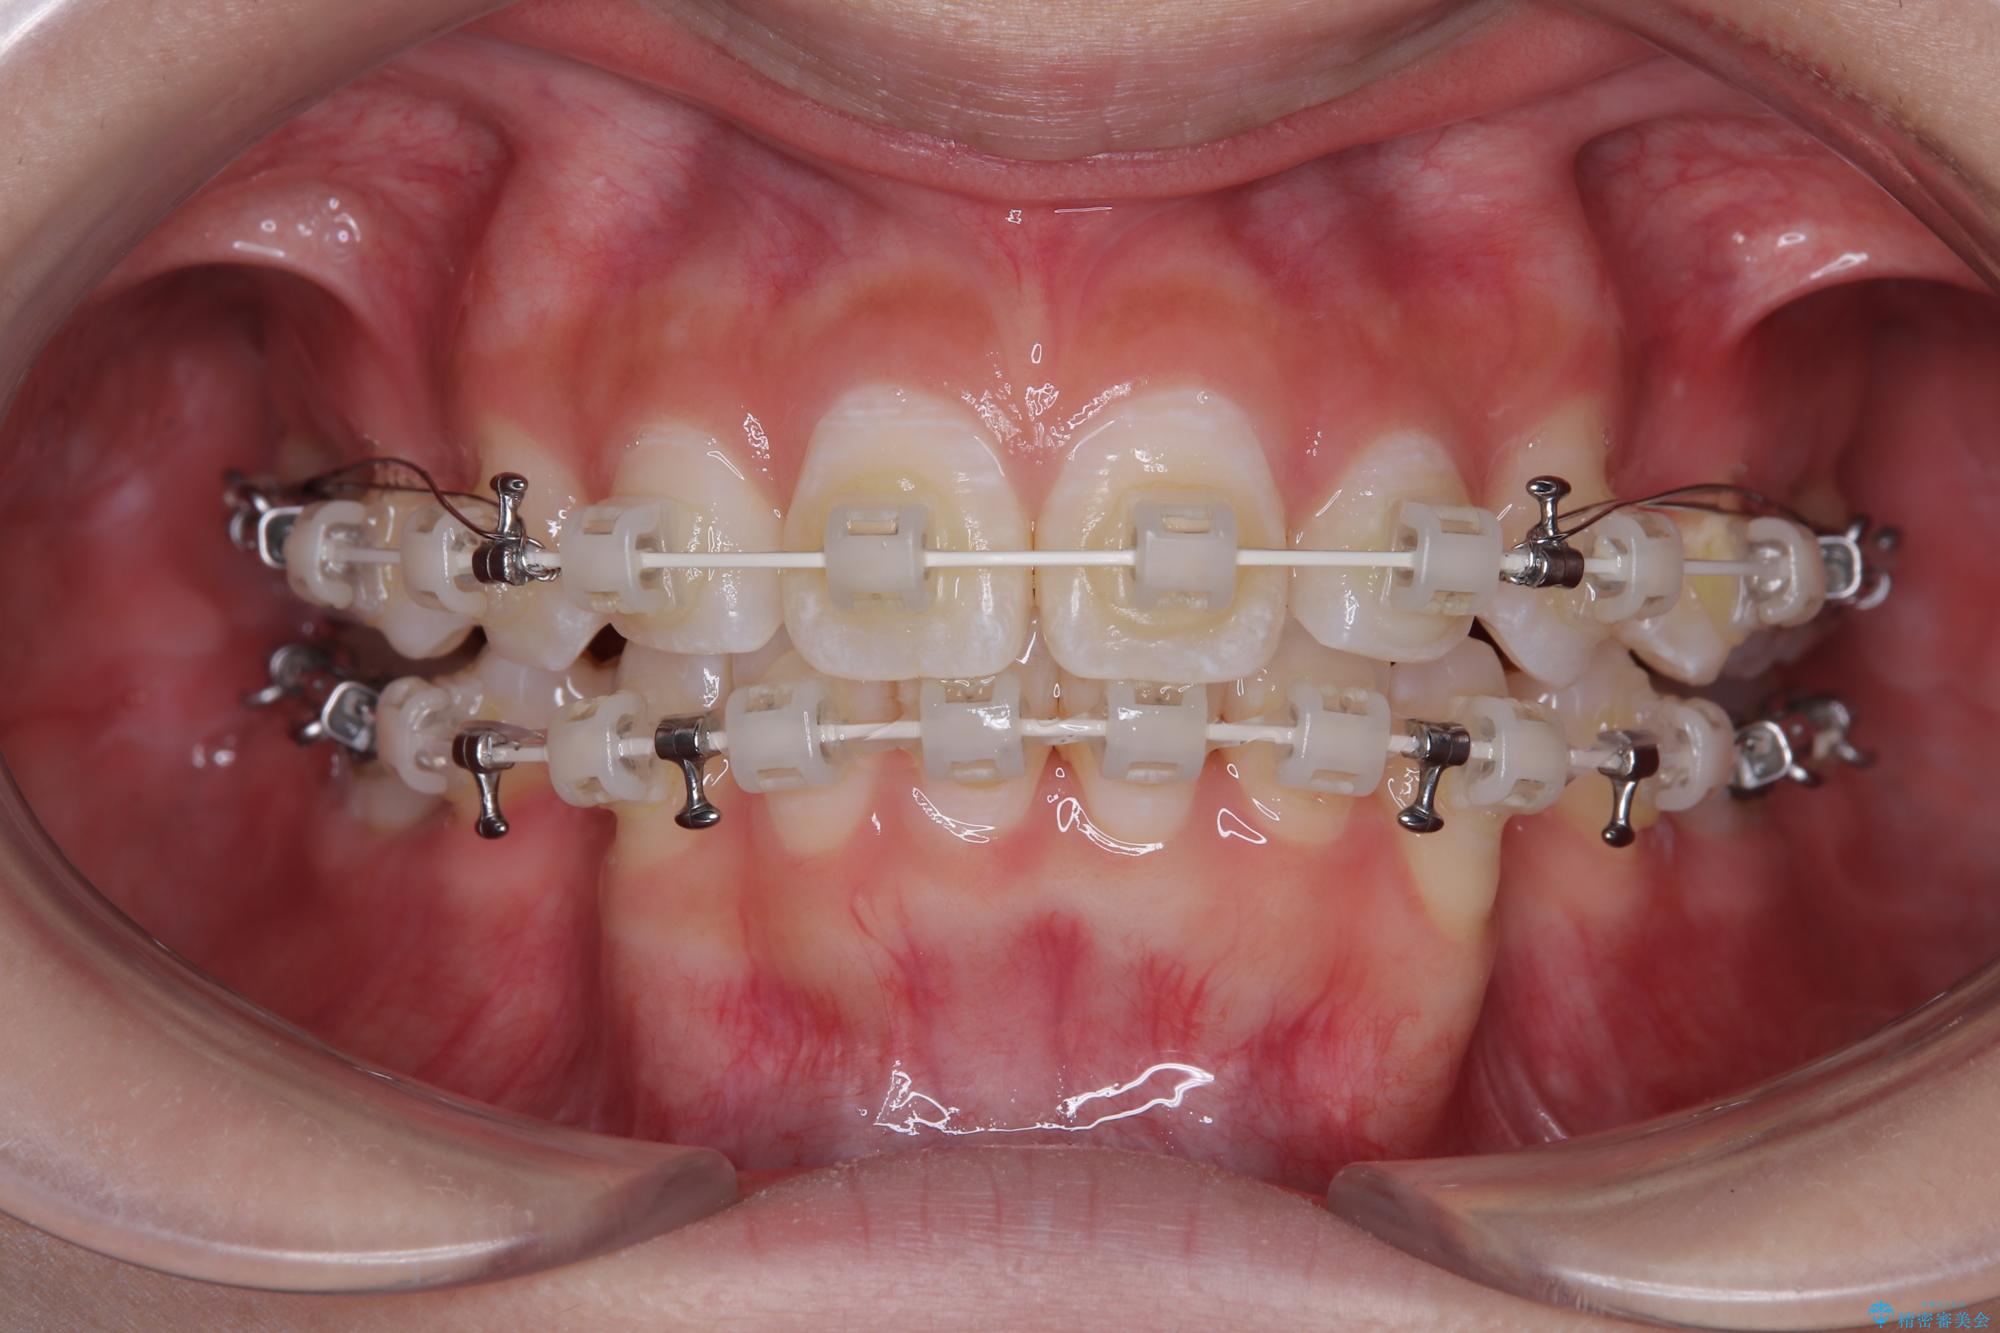

- 矯正装置

- 審美装置

- 口を閉じたときに飛び出してしまう上顎前歯を気にして来院された患者様です。

下顎はデコボコが気になっていたため、上下左右第一小臼歯4本を抜去して、ワイヤー装置にて口元の突出感を改善するよう矯正治療を行うこととしました。